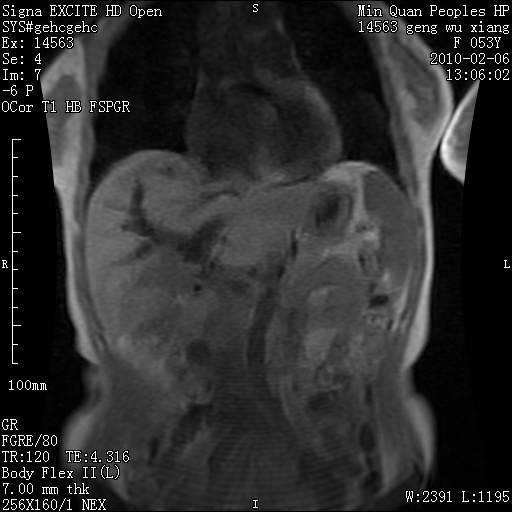

标题: MRI2762:胆道梗阻原因?

f,53y,全身黄染多日。

高位胆道梗阻 胆管癌可能性大

支持 高位胆道梗阻 胆管癌可能性大。